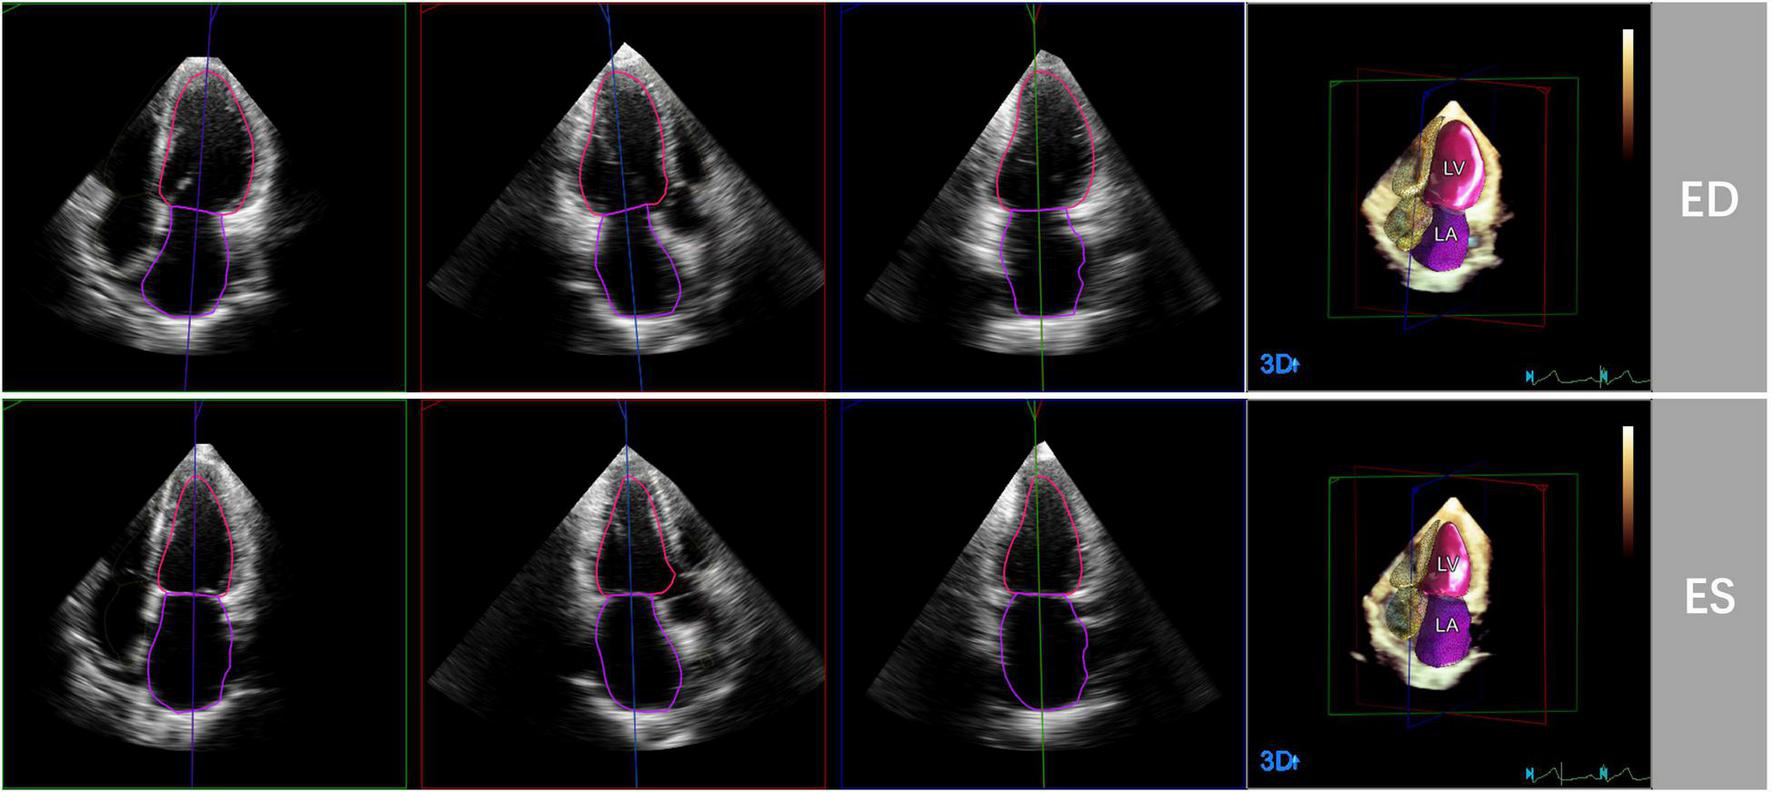

3D echocardiographic acquisitions were also analyzed by the HeartModel software. This algorithm is able to automatically detect LV and LA endocardial borders at end-diastole and end-systole and measure LVEDV, LVESV, LVEF, LAVmax and LAVmin (Figure 1). Observers can freely move the adjustable slider to optimize cardiac chamber border identification according to their preference, including global and regional editing.

FIGURE 1

Representative case of automated 3D echocardiographic analysis for left heart chamber quantification. Left heart chambers’ endocardial borders were automatically detected by the Heart Model software at end-diastole (ED) and end-systole (ES) in apical four-, three-, and two chamber sections.